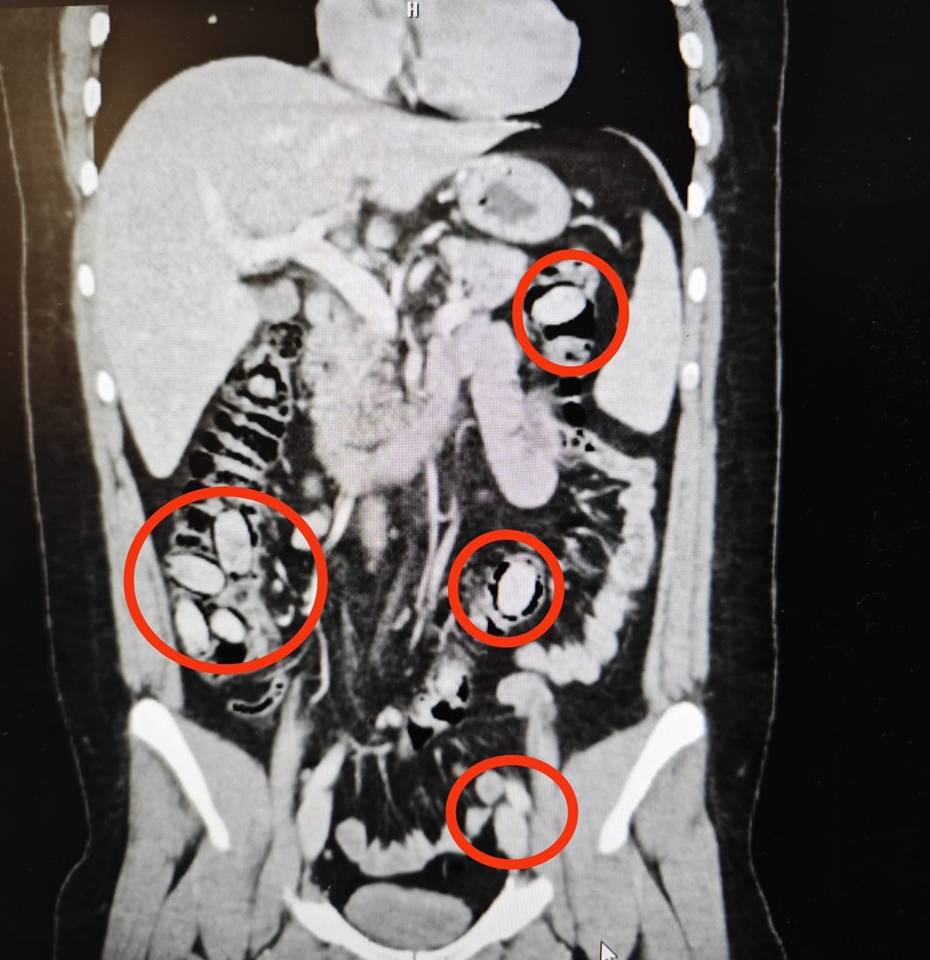

Yurtdışından Eskişehir'e gelen S.A. (25) isimli yabancı uyruklu şahsın kent girişindeki çevirme noktasında durumundan şüphelenilmesi üzerine hastanede yapılan detaylı tetkikler neticesinde yutmak suretiyle midesinde 44 kapsül metamfetamin maddesi taşıdığı anlaşıldı. Cerrahi müdahaleyle sözkonusu maddeler şahsın bedeninden çıkarıldı. Tedavisi akabinde şahıs tutuklandı.